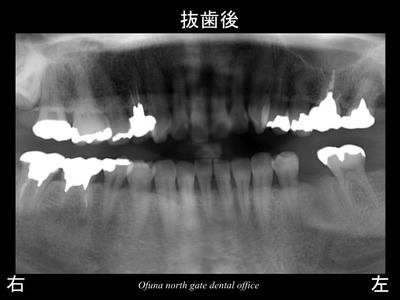

以下は、抜歯後です。

この患者様は、神経がない歯が非常に多いことが分かります。